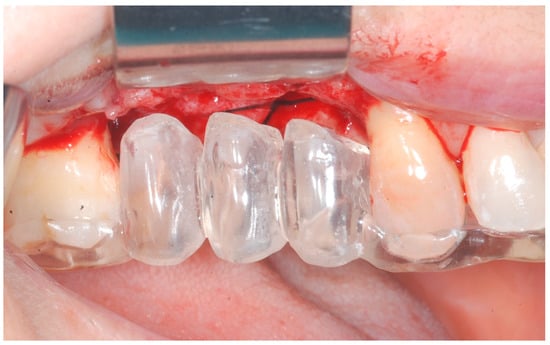

Local anesthesia was obtained with mepivacaine 20 mg/mL with epinephrine 1:100.000 (Optocain, Molteni Dental, Milan, Italy) injections. To raise a mucoperiosteal flap, a crestal incision followed by oblique releasing incisions were made to allow for a wide flap basis as well as sufficient access to the defective ridge area. The flaps were carefully raised using tissue elevators. The bone ridge was examined and any soft tissues remaining on the crest were meticulously removed with a surgical curette (Figure 2).

Figure 2. Trapezoidal flap elevation and initial bone thickness.

Medicina 61 01814 g002

Figure 3. Surgical stent used for implant positioning.